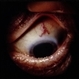

- Ciliary Body Melanoma

- Jason S. Calhoun, Department of Ophthalmology, Mayo Clinic Jacksonville, Florida

- Imaging device

- Photo slit lamp biomicroscope

- 71-year-old male who was recently diagnosed with a large ciliary body melanoma that is pushing into the anterior chamber of the left eye. Patient is going to proceed with proton therapy.